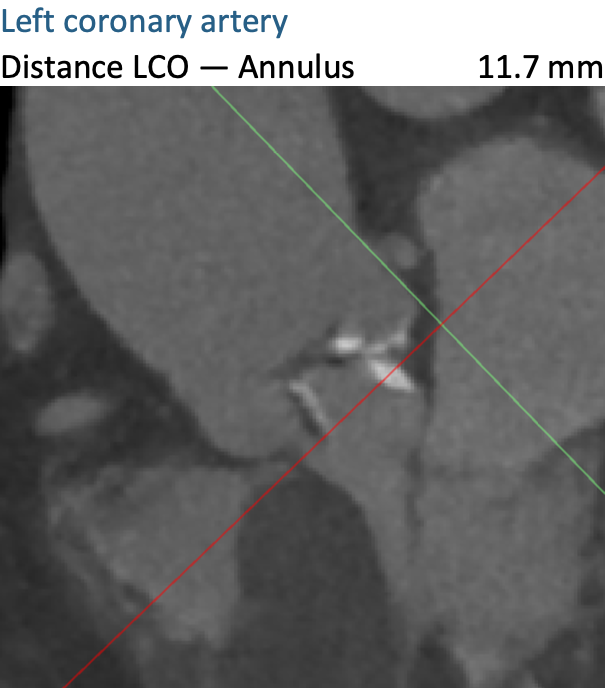

通过FEops评估冠脉风险

根据FEops报告上的左右冠脉CT截面得知RCA Height:17.6mm、LCA Height:11.7mm,左冠脉高度小于12mm是存在一定阻塞风险的,但是通过植入前后的3D模型对比瓣叶形态得知冠脉风险比较低。